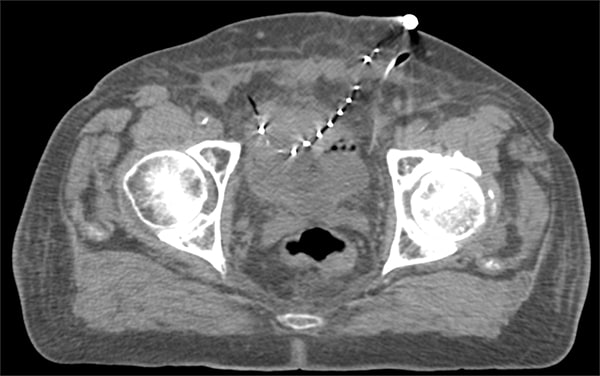

通过腹腔镜和膀胱镜联合,观察膀胱壁两侧。使用腹腔镜器械,清理膀胱壁以便后续插入导管,使用钛夹标记临床靶体积(CTV)边界,沿膀胱壁平行植入三至四根近距离治疗导管。导管两个末端均从患者皮肤中穿出

确定施源器相对于肿瘤和危及器官的位置